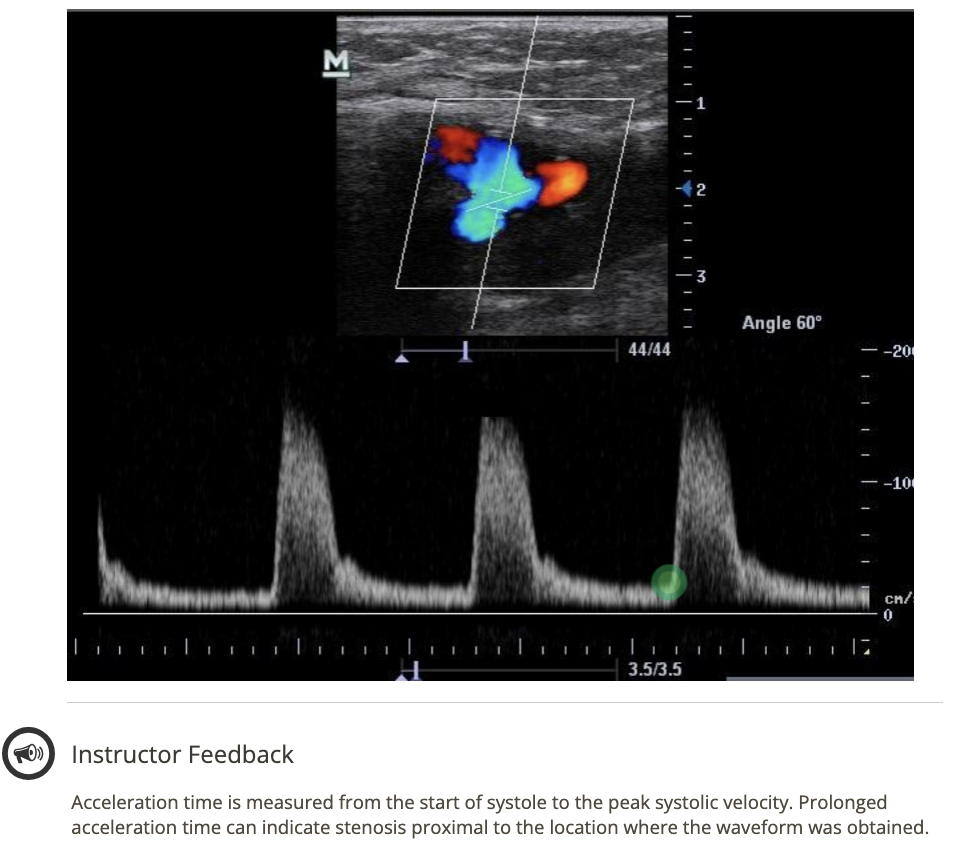

![<p>where does the 1st caliper go when measuring acceleration time? click on the 3rd waveform</p><p>.</p><p>[start of 3rd waveform]</p>](https://knowt-user-attachments.s3.amazonaws.com/10a2a0eb-5b9b-4269-8bf3-eb6e5f0a21bd.png)

where does the 1st caliper go when measuring acceleration time? click on the 3rd waveform

.

[start of 3rd waveform]

start of 3rd waveform